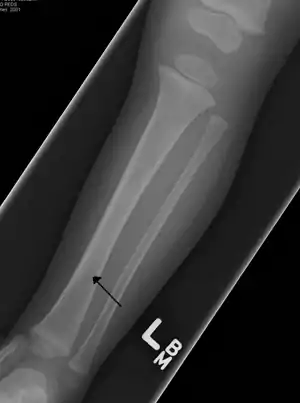

Toddler's fractures are bone fractures of the distal (lower) part of the shin bone (tibia) in toddlers (aged 9 months-3 years) and other young children (less than 8 years).[1] The fracture is found in the distal two thirds of the tibia in 95% of cases,[1] is undisplaced and has a spiral pattern. It occurs after low-energy trauma, sometimes with a rotational component.

| A toddler's fracture | |

Typical symptoms include pain, refusing to walk or bear weight and limping -bruising and deformity are absent. On clinical examination, there can be warmth and swelling over the fracture area, as well as pain on bending the foot upwards (dorsiflexion). The initial radiographical images may be inconspicuous (a faint oblique line) and often even completely normal.[3] After 1–2 weeks however, callus formation develops. The condition can be mistaken for osteomyelitis, transient synovitis or even child abuse. Contrary to CAST fractures, non-accidental injury typically affect the upper two-thirds or midshaft of the tibia.